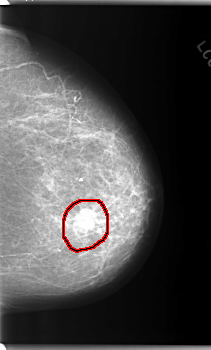

C_0204_1.LEFT_MLO

LEFT_MLO LINES 5896 PIXELS_PER_LINE 3568 BITS_PER_PIXEL 12 RESOLUTION 50 OVERLAY

FILE: C_0204_1.LEFT_MLO.OVERLAY

TOTAL_ABNORMALITIES 1

ABNORMALITY 1

LESION_TYPE MASS SHAPE LOBULATED MARGINS MICROLOBULATED

ASSESSMENT 5

SUBTLETY 5

PATHOLOGY MALIGNANT

TOTAL_OUTLINES 1

BOUNDARY